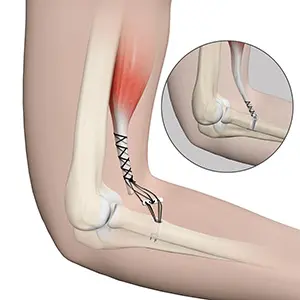

Elbow Fracture Reconstruction

Elbow fracture reconstruction is a surgical procedure employed to repair and restore the appearance and full function of a damaged elbow caused by severe trauma or injury.

Elbow Fractures

Elbow fractures may occur from trauma, resulting from various reasons: a fall on an outstretched arm, a direct blow to the elbow or an abnormal twist to the joint beyond its functional limit.